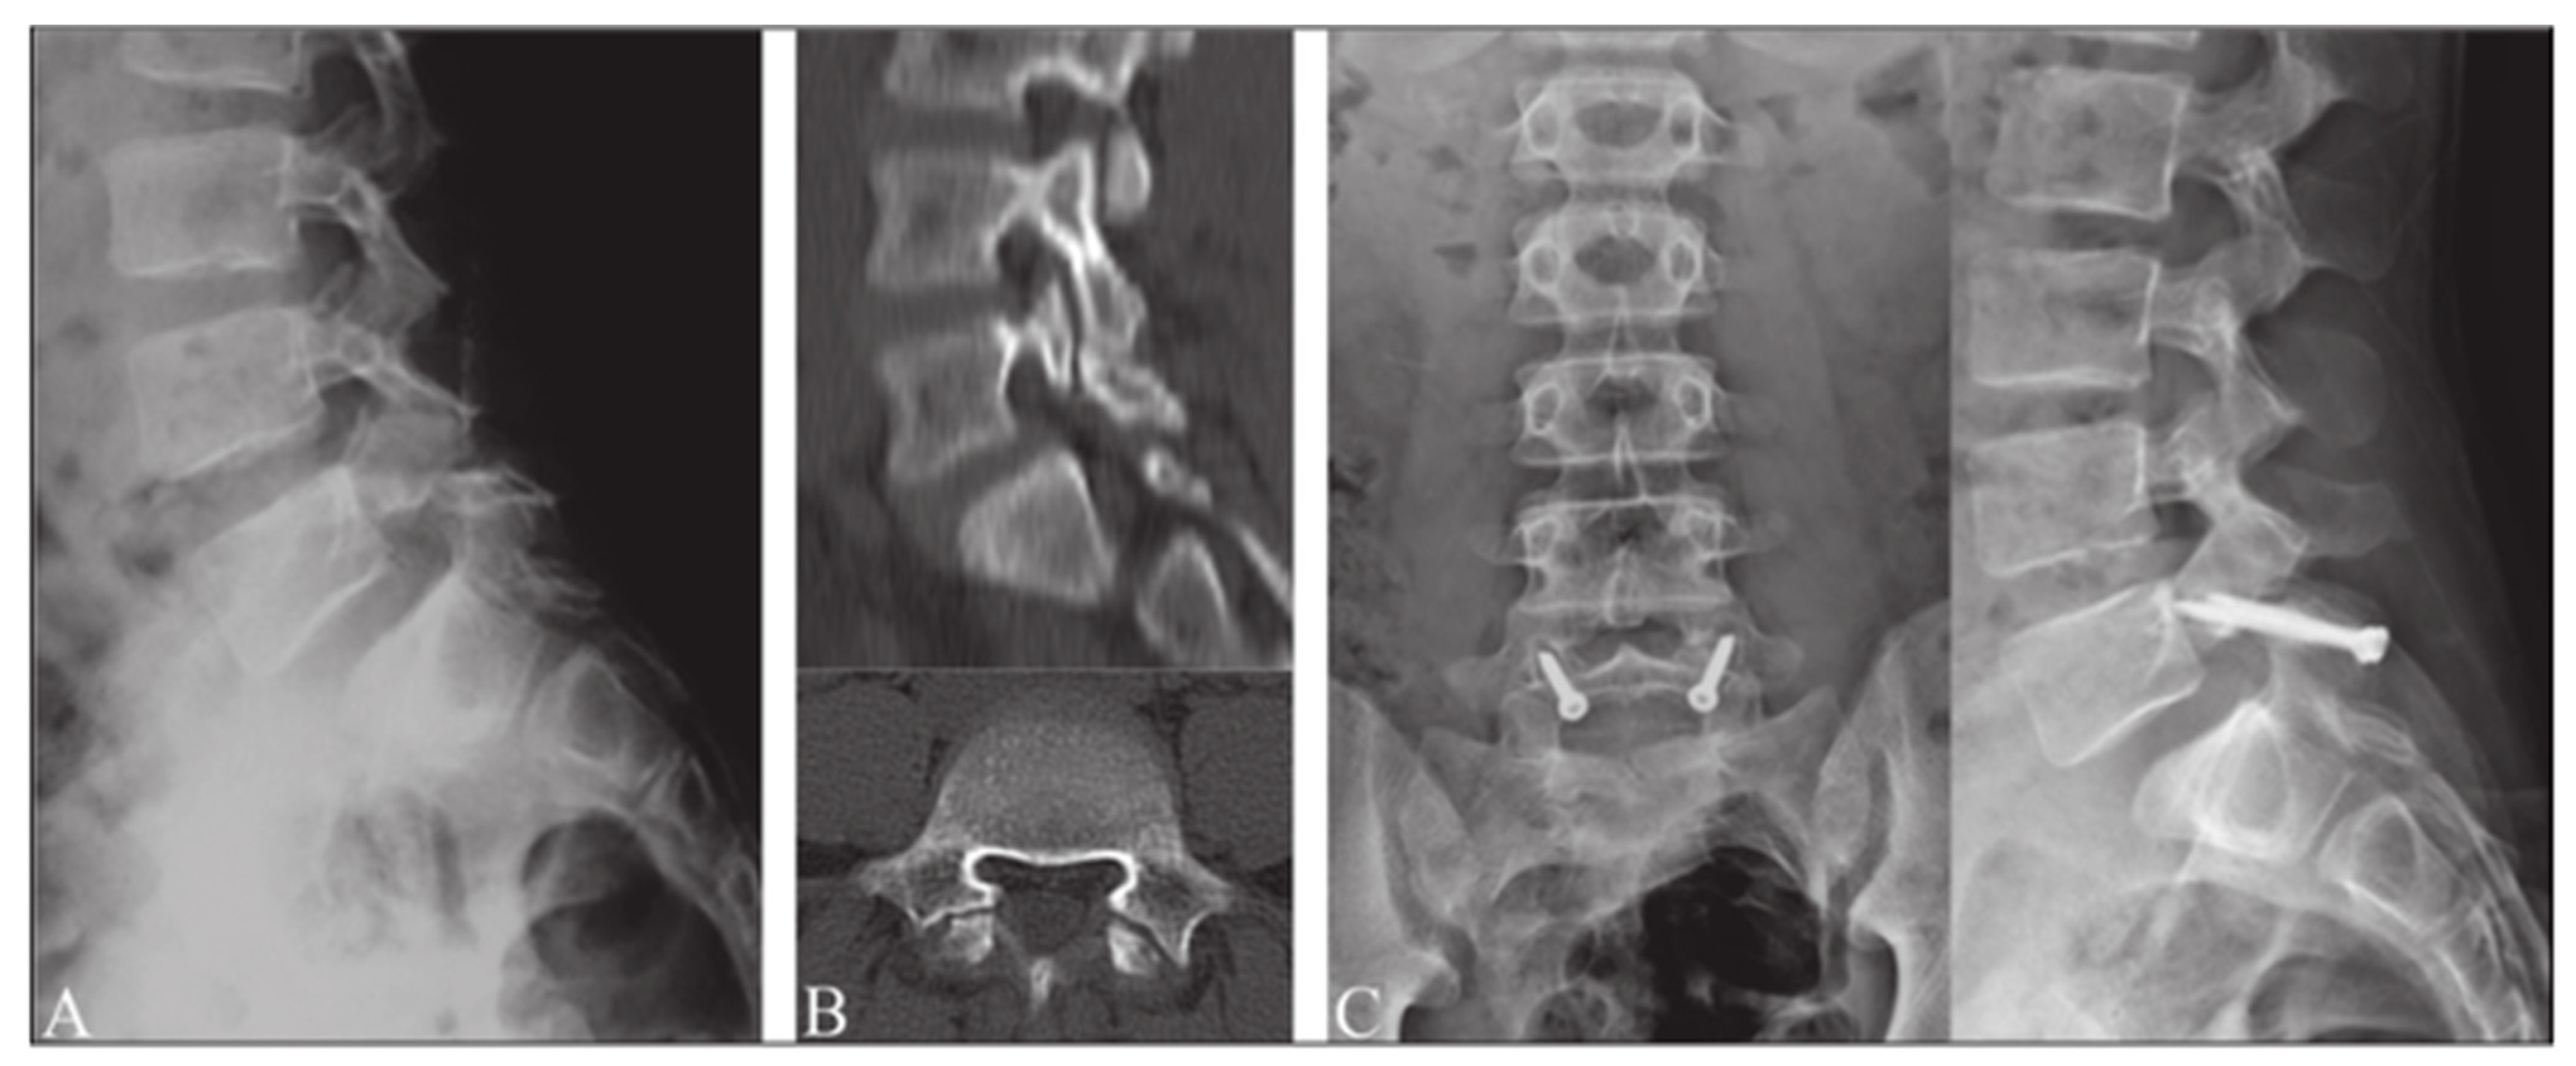

Levi Technique—Minimally Invasive Direct Pars Screw Placement